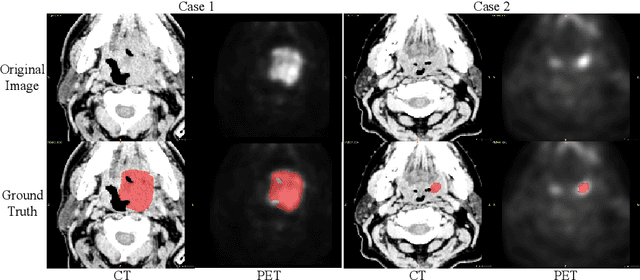

Abstract:Automatic segmentation of head and neck tumors plays an important role in radiomics analysis. In this short paper, we propose an automatic segmentation method for head and neck tumors from PET and CT images based on the combination of convolutional neural networks (CNNs) and hybrid active contours. Specifically, we first introduce a multi-channel 3D U-Net to segment the tumor with the concatenated PET and CT images. Then, we estimate the segmentation uncertainty by model ensembles and define a segmentation quality score to select the cases with high uncertainties. Finally, we develop a hybrid active contour model to refine the high uncertainty cases. Our method ranked second place in the MICCAI 2020 HECKTOR challenge with average Dice Similarity Coefficient, precision, and recall of 0.752, 0.838, and 0.717, respectively.